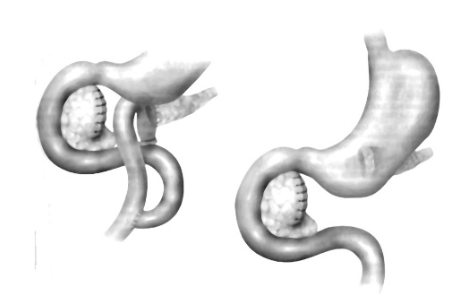

Phẫu thuật nối tụy – hỗng tràng

Phẫu thuật nối tụy – dạ dày

Phẫu thuật bảo tồn chấn thương tụy

- Tụ máu, dập nát nhưng ống tụy chính chưa tổn thương:- Cầm máu, dẫn lưu HCMN

- Đứt ống tụy chính (bên trái TMMTTT):- Nối tụy – hỗng tràng: Beger, Roux-en-Y

- Nối tụy – dạ dày

Phẫu thuật cắt tụy trung tâm

Cắt tụy trung tâm, nối tụy với mặt sau dạ dày

Phẫu thuật cắt bỏ đầu tụy, bảo tồn tá tràng

Cắt bỏ đầu tuỵ bảo tồn tá tràng và nối tuỵ ruột Roux en Y (theo Beger H.G. 1985)